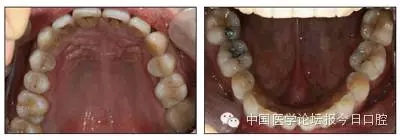

口內(nèi)情況:恒牙列,24、34、44缺失,磨牙Ⅲ類關(guān)系,上牙列散隙,上前牙扇形漂移。前牙深覆(牙合)、深覆蓋??谇恍l(wèi)生較差,11與12間牙齦乳頭紅腫,多個(gè)牙探診有牙周袋形成,11松動(dòng)Ⅰ度,余切牙松動(dòng)(-),患者面像及口內(nèi)像如圖1、2所示。

圖2 治療前口內(nèi)像